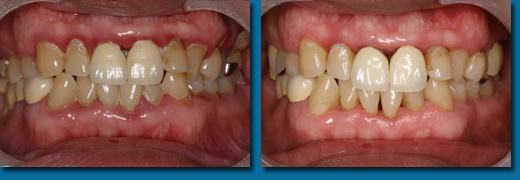

歯の磨き方が悪いと虫歯にもなりますが、磨き残した歯垢が唾液と反応して硬い歯石になって歯にこびり付いてしまいます。歯石になると歯ブラシでは取れなくなり、その中には沢山のバイ菌が潜んでいるために周りの歯肉が赤く腫れてしまいます。歯ブラシがあたると出血しやすくなりそのまま放置すると歯槽のう漏に進行していきます。歯石の除去を行い毎日の歯磨きをしっかり行うことで歯肉の状態はビックリするぐらい良くなります。歯石の除去は歯科衛生士の上手い下手が最も出る部分で、当院の歯科衛生士も歯石の取り残しがないように日々努力しています。左が歯石を取る前、右が取った後です。